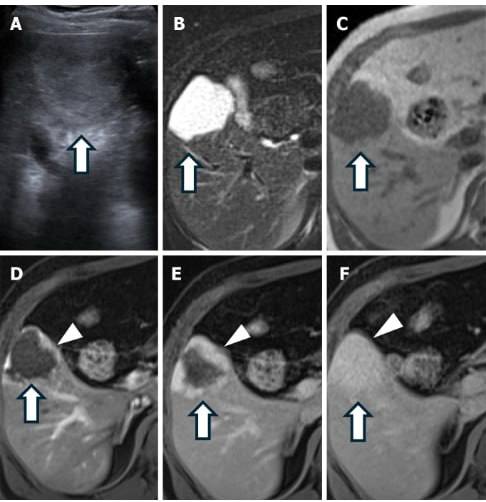

ضایعات بدخیم کبدی و مدیریت آنها: در میان ضایعات بدخیم کبد، کارسینوم هپاتوسلولار (HCC) شایعترین نوع سرطان اولیه کبد است که اغلب در بیماران مبتلا به سیروز یا عفونت مزمن ویروسی کبد دیده میشود. در تصویربرداری CT و